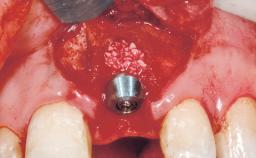

A 30-year-old female patient had lost tooth 21 and was referred to our clinic for consultation and treatment. Due to advanced apical infection, tooth 21 had been extracted two months earlier at another clinic and an acrylic-resin tooth had been bonded to the adjacent teeth. The patient desired implant treatment to avoid any damage to the adjacent natural teeth. While the patient had no history of any systemic disorder, she was a heavy smoker and exhibited medium to advanced periodontitis in the entire jaw. After the initial treatment to achieve a pocket probing depth of less than 4 mm and no bleeding on probing, a decrease in the height of the papillae mesial and distal to the extraction site and overall gingival recession were observed.

Bone Augmentation Horizontal|Staged

Augmentation Materials Autogenous chips|Membrane

Placement Protocol Early or late implant placement